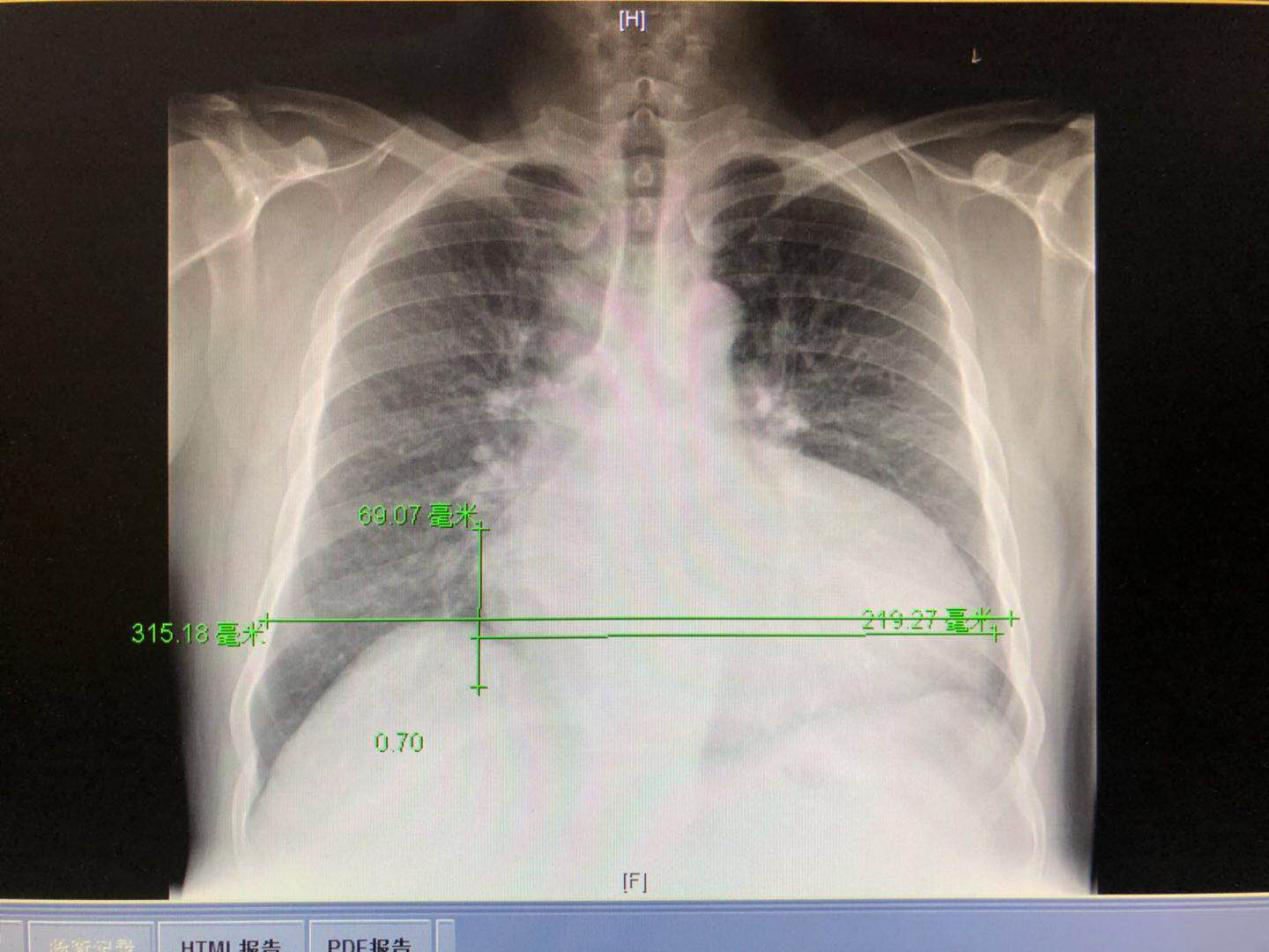

胸片:

2018-3-19左心受累疾患,左心功能不全。